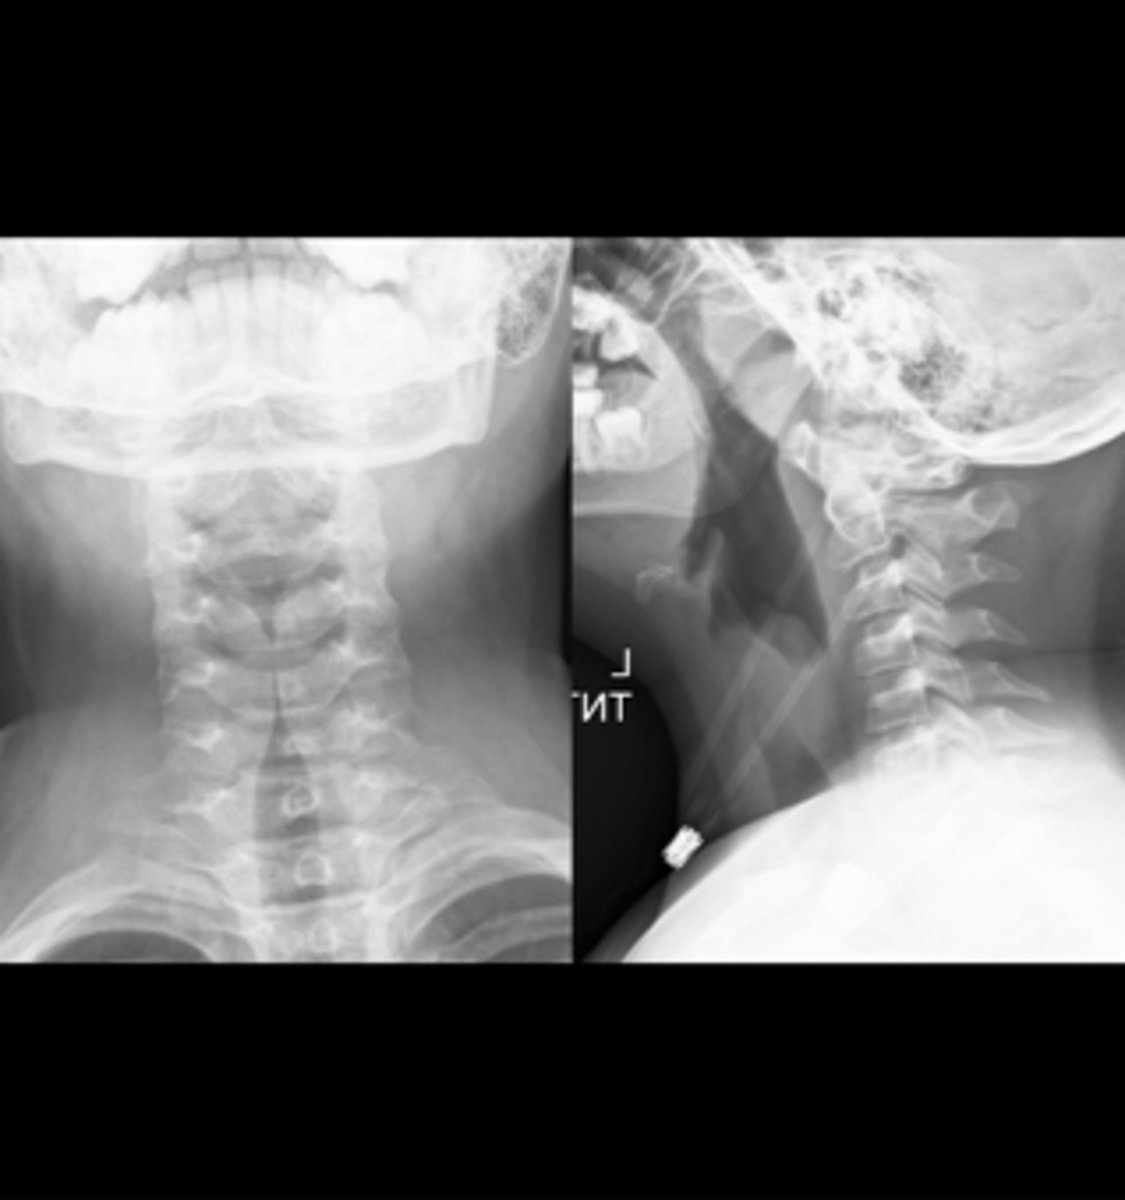

steeple sign (croup)

knowt flashcard image

43

New cards

Steeple sign- group